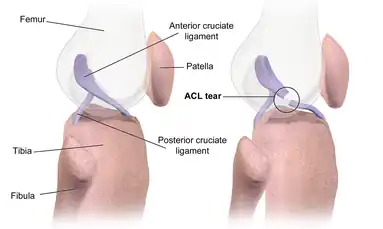

Structure of the knee and the ACL

An ACL rupture is the most common injury that takes place in the knee. The ACL is very small; the average length is 38mm and only 11mm wide. The knee is formed by the connection of the femur (upper leg bone) and the tibia (lower leg bone) with another two bones been the fibula (small bone next to the tibia) and the patella (the kneecap). Within these two main bones tendons attach the bones to the muscles that give the knee movement, while the ligaments provide the knee with stability. The ACL looks like a mixture of an oval and triangle shape, and is located in a very compact area within the knee. The ACL fibres are in place to give direction for the knee to move, such as a kicking or twisting motion. If an ACL rupture occurs, it immediately forces an increase not only to the anterior tibial translation but also the internal tibial rotation. This is because, as the femur is pushed back to rotate, trauma is caused to the knee due to a lack of stabilisation. The ACL is there to create rotational stability within the knee to be able to produce different motions. Importantly, the ACL restrains the anterior tibial translation, providing 85–87% total restraining force.[3]